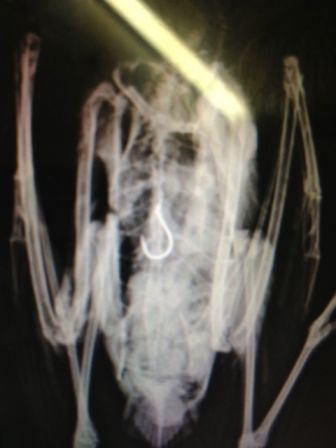

Nobody knows how long poor little Nelson the Seagull had been suffering with a fishing hook inside him.

This X-ray clearly shows the fishing hook in his digestive tract.